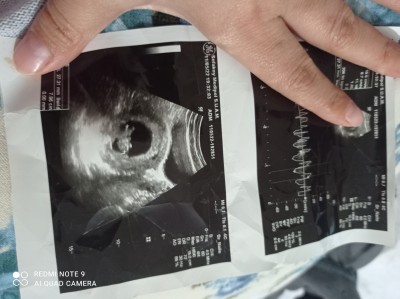

11haftalik hamileyim daha cinsiyet öğrenemedik İlk çocuğum kızdi çok rahat geçti şimdi bu ikincisi çok sıkıntılı geçiyor cinsiyetini de çok merak ediyorum lütfen yardımcı olur musunuz

Gebelik haftası 11